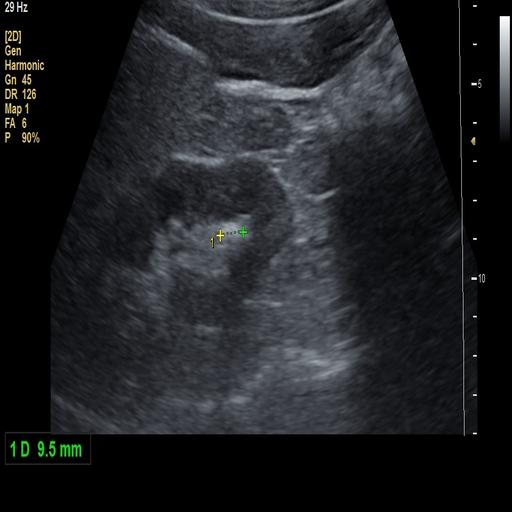

数据样例

结石肾脏样例

- 肾结石在超声图像中主要表现为高回声点,并伴随声学阴影,其形态和位置因结石大小、位置及患者体质不同而变化。

数据集附带系统化的标注指南,涵盖肾结石超声典型特征的识别方法,包括高回声点、声学阴影、边缘特征等。